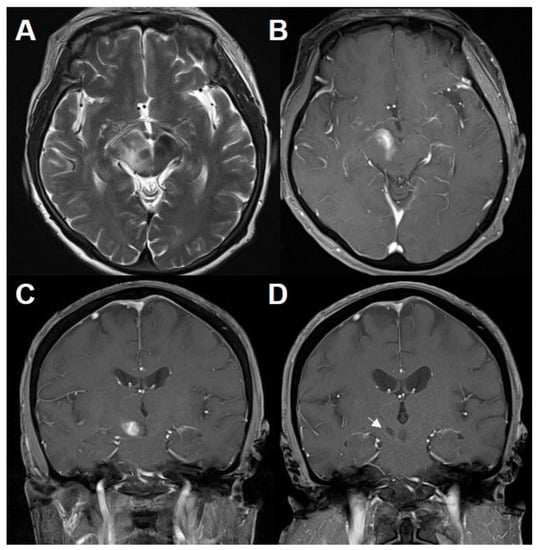

A 70-year-old woman without previous medical history presented with a one-week history of numbness in the left side of face, arm, and leg. A neurologic examination revealed no additional neurologic sign except above-mentioned symptoms. There were no abnormal laboratory findings from blood samples. Brain MRI showed a contrast-enhancing lesion in the ventral portion of the right midbrain with perilesional edema (Figure 1A–C).

Figure 1.

MRI of a preceding inflammatory lesion. T2-weighted (A) and T1-weighted MRI with gadolinium (B,C) showing an enhancing lesion in the ventral portion of the right midbrain with perilesional edema. Follow-up T1-weighted MRI with gadolinium (D) after steroid therapy demonstrating the proper location of biopsy (white arrow).

Brain computed tomography (CT) and MRI were performed after the biopsy procedure. Proper specimens were sampled with minimal hemorrhage (Figure 1D). After careful consideration, the patient was treated with intravenous methylprednisolone 160 mg daily for 5 days, leading to subsidence of symptoms gradually. Subsequently, daily doses of 10 mg oral prednisolone were introduced for remaining mild symptoms. Three months after the initial brain MRI, there was nearly complete resolution of the lesion. Brain MRI was performed at 6-month interval and did not reveal specific pathologic findings. Twenty-six months after the initial attack, she suddenly developed urinary incontinence, quadriparesis, and mental deepening. Brain MRI showed homogenously enhancing lesions in both cerebral hemispheres and a curvilinear enhancing lesion involving the middle cerebellar peduncle, distant from the initial lesion (Figure 3A–C).